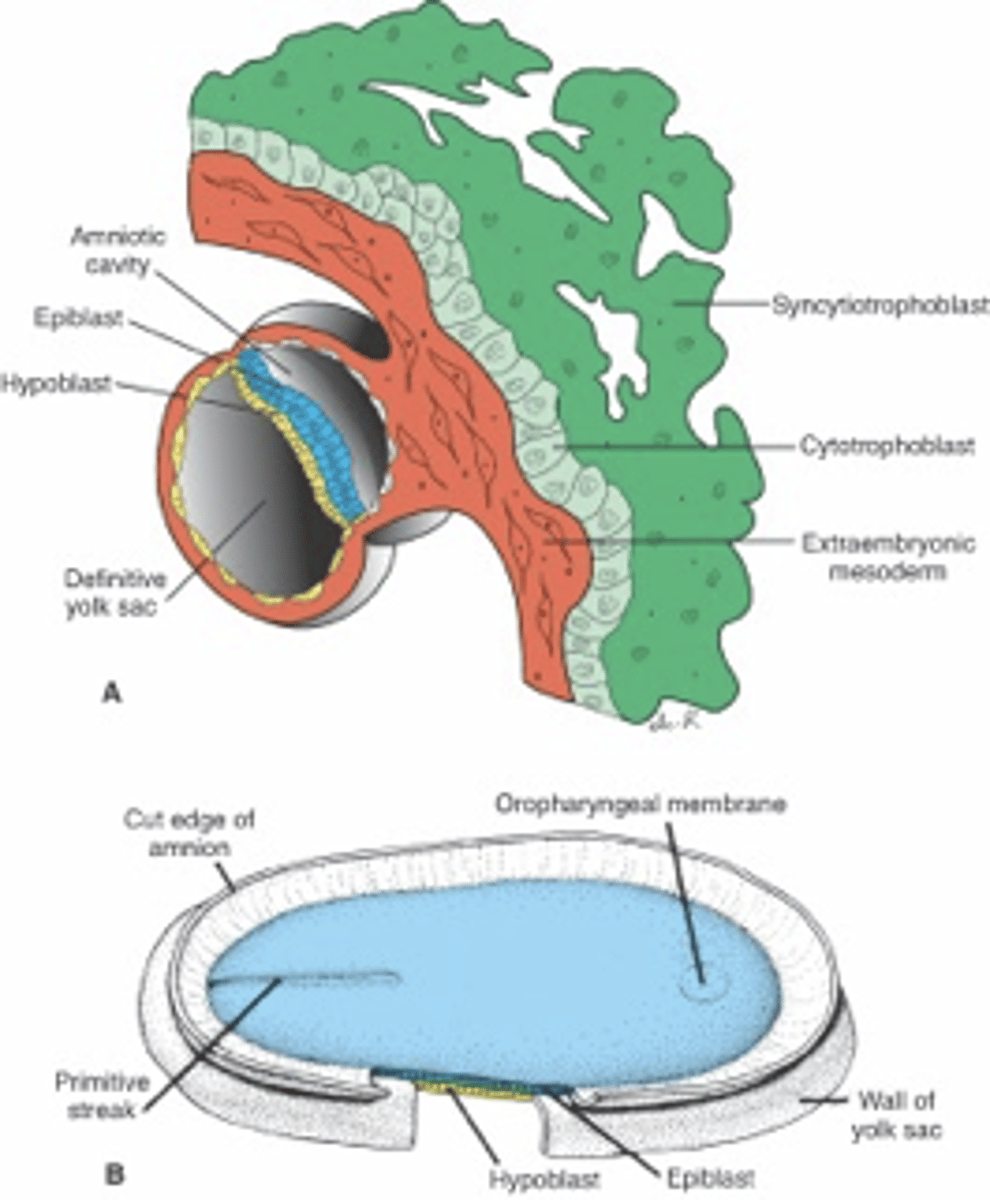

the inner cell mass of the blastocyst will differentiate into the __________ and _____________ which forms a __________ disc

hypoblast, epiblast, bilaminar

the (epiblast/hypoblast/trophoblast) is the source of all 3 germ layers. the 3 germ layers are established during _______________. describe how these layers are formed?

epiblast, gastrulation;

after a primitive streak forms on the epiblast, epiblast cells migrate toward the streak and invaginate into it to first create the endoderm, then the mesoderm. the ectoderm is the remaining cells in the epiblast.